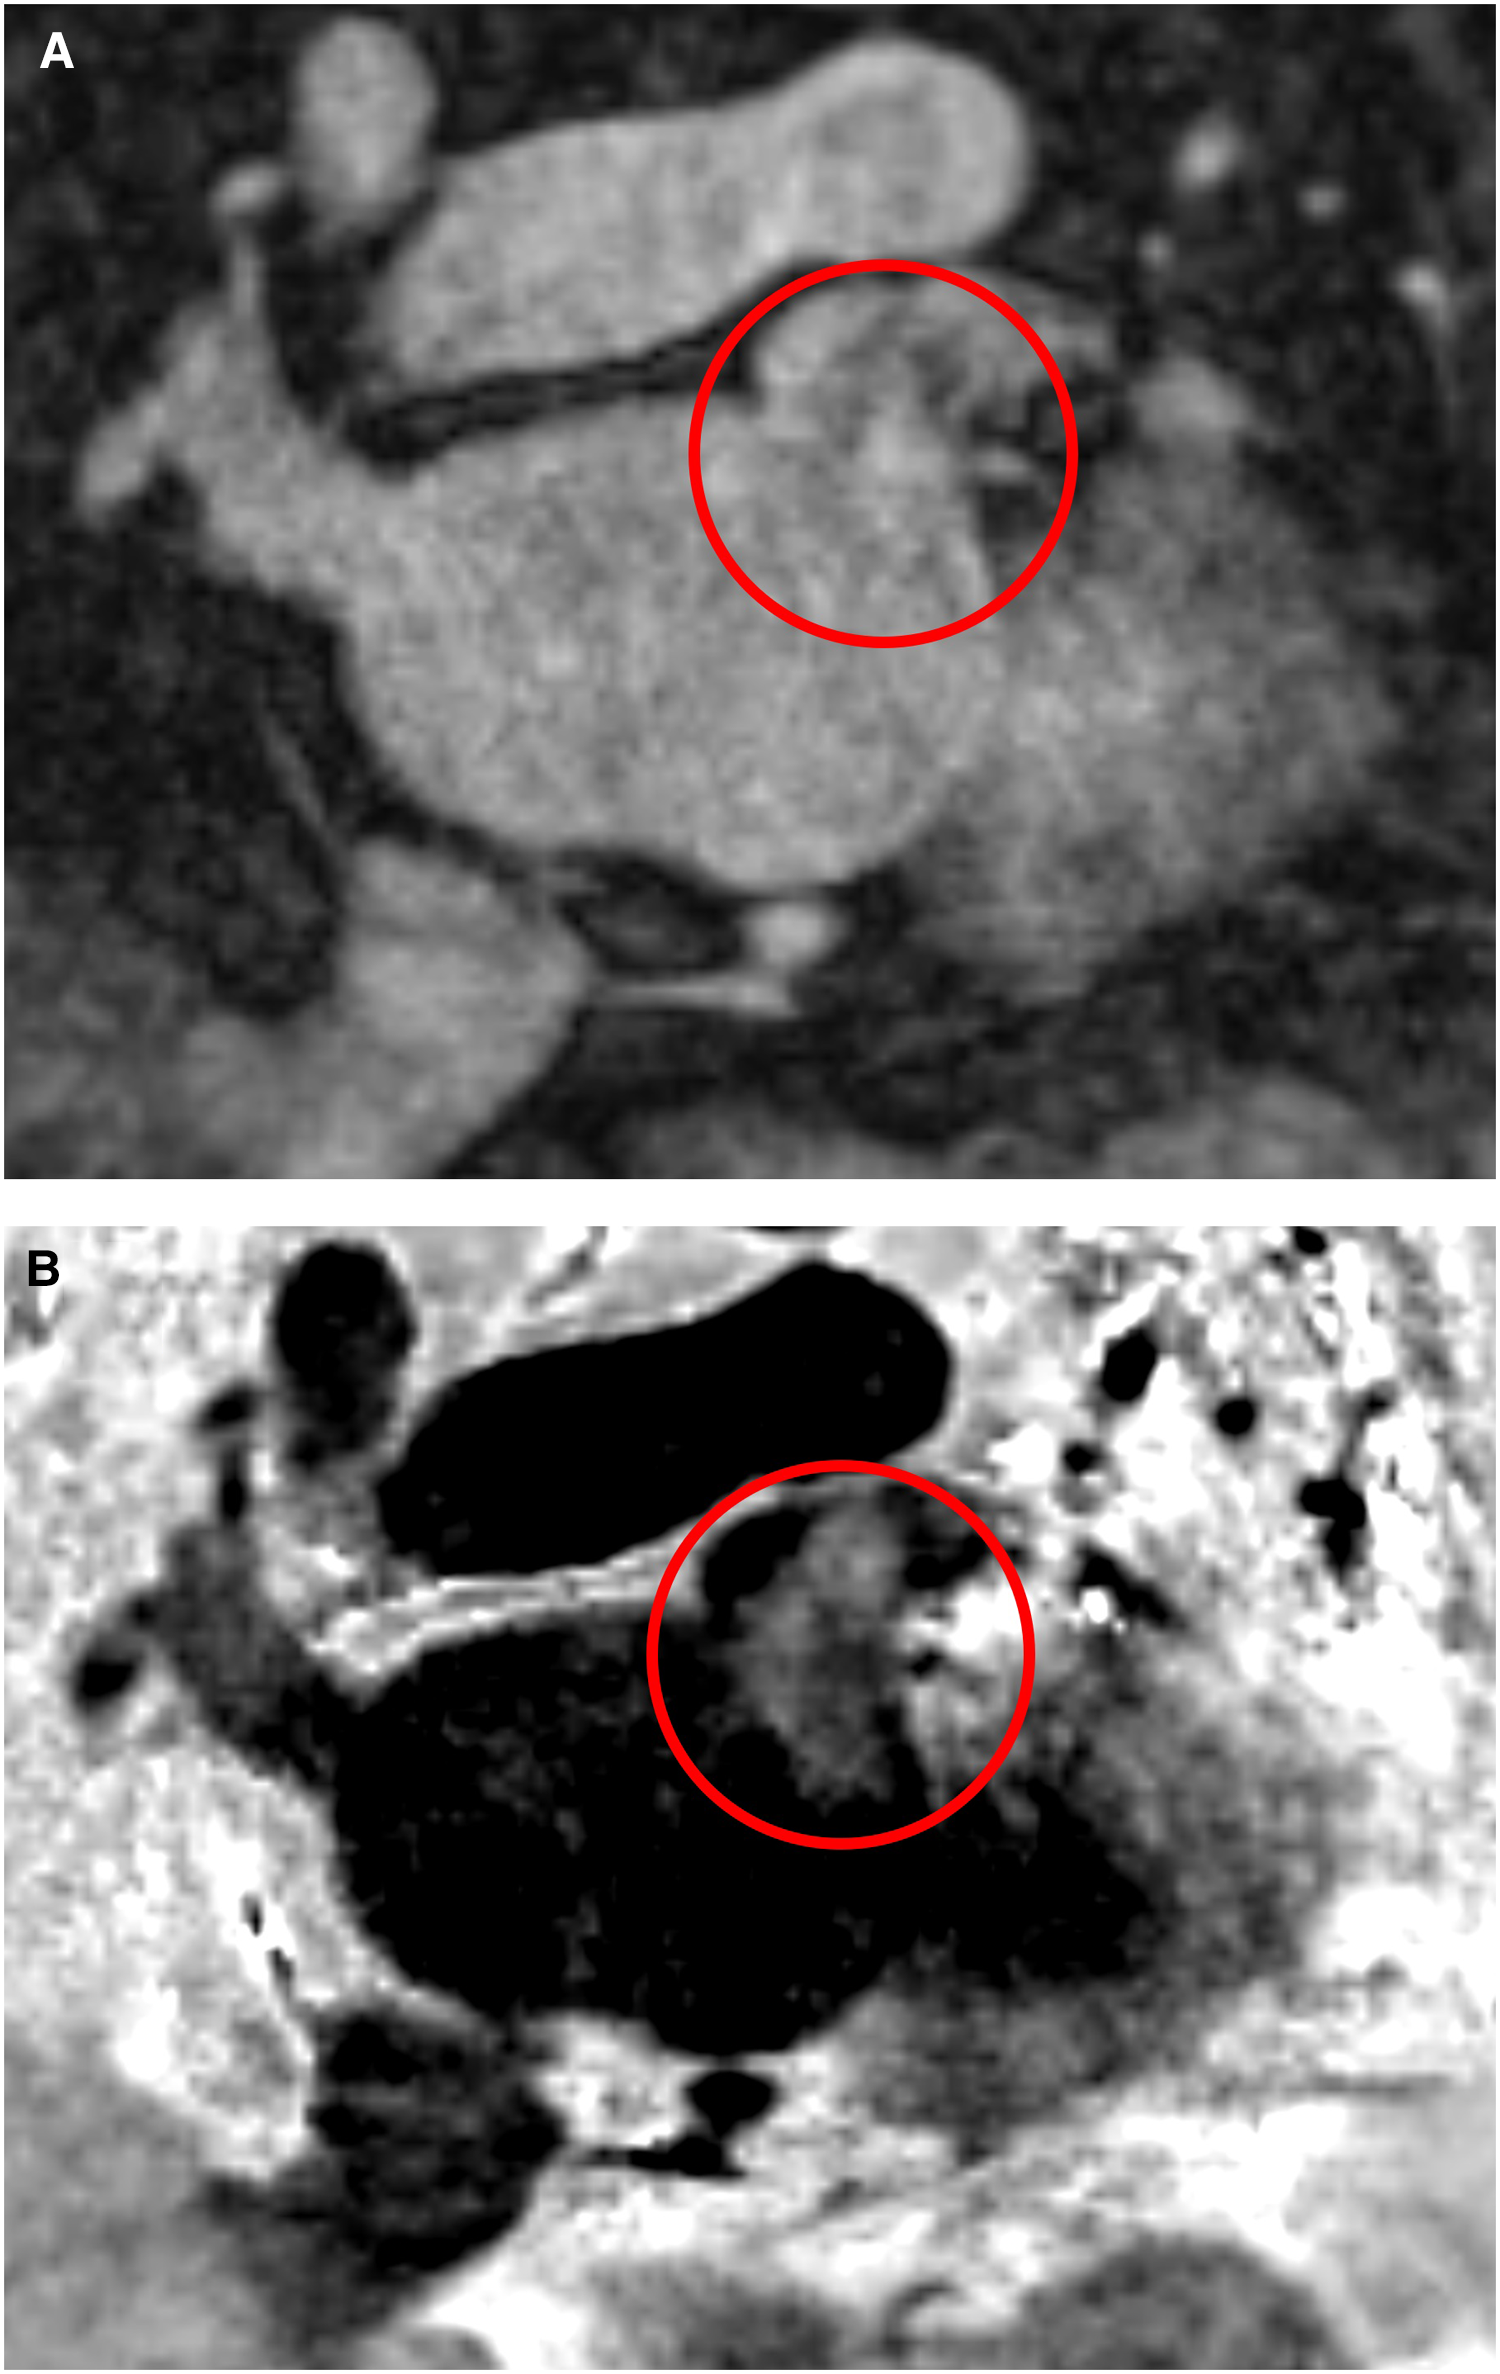

In summary, the new BOOST sequence is suitable for detecting larger thrombi, but its effectiveness in detecting or excluding smaller thrombi may be limited with the used spatial resolution settings. As we used an isotropic resolution of 1.4 × 1.4 × 1.4 mm in BOOST measurements, it is possible that the use of a higher resolution (1.2 × 1.2 × 1.2 mm) could improve its effectiveness in detecting smaller thrombi. Thus, further studies will be needed to characterize the sequence more accurately in LAA thrombus detection. The ability to detect larger thrombi is also supported by the case of a patient who was examined with the BOOST CMR sequence outside the scope of this study (Figure 4). Although the BOOST image was performed with MT-preparation (MTC), which is not the most suitable for thrombus detection, the large thrombus located in the left atrium is clearly visible.

Figure 4

Left atrial appendage thrombus circled in red on CMR MT-preparation (MTC) BOOST sequence images. Panel (A): Bright-blood image of MTC BOOST. Panel (B): Dark-blood image of MTC BOOST (Heart and Vascular Center, Semmelweis University).